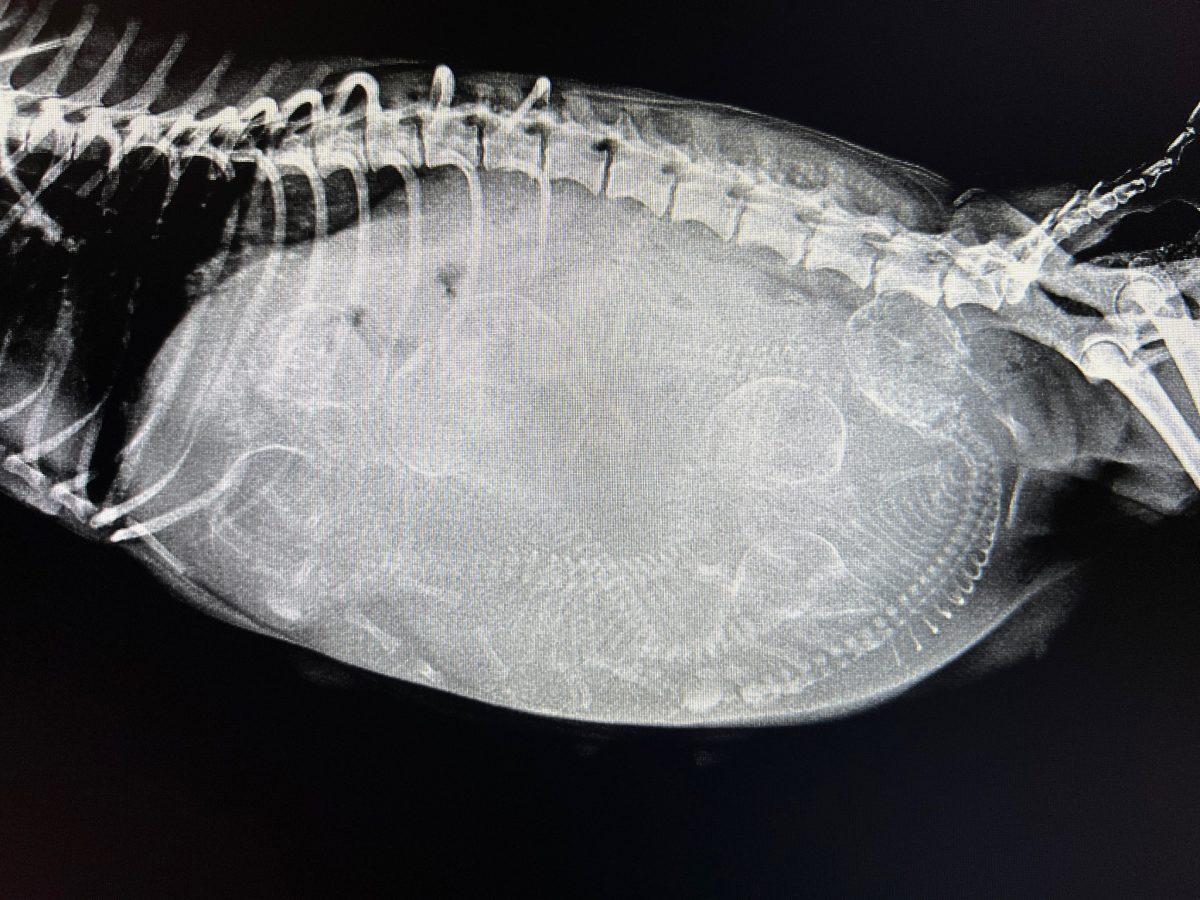

Lily’s first stop was the Companion Animal Hospital in Wicker Park, Chicago. X-rays revealed she was carrying seven puppies.

Source: Trio Animal Foundation